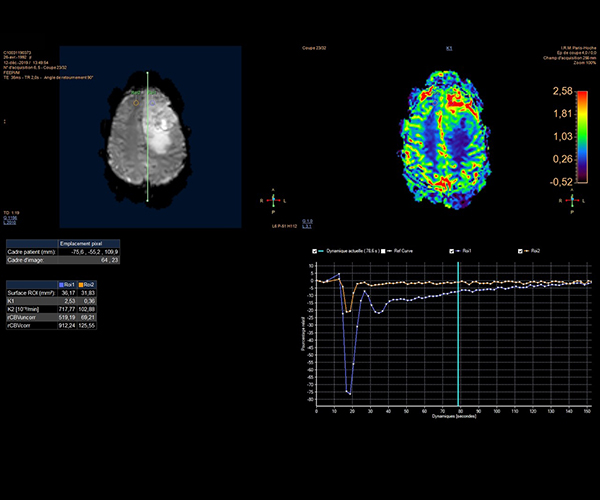

L’augmentation de l’effet de susceptibilité magnétique à plus haut champ permet d’améliorer la détection des hémorragies et est utilisé également dans l’imagerie de perfusion (tumeurs) et l’IRM fonctionnelle (BOLD). L’allongement du T1 à plus haut champ entraîne une meilleure saturation des tissus statiques et par conséquent une augmentation du contraste sang/tissus dans l’AngioIRM.

La séquence de perfusion par marquage des spins artériels (ASL) étudiant la perfusion cérébrale sans injection trouve pleinement son application à 3T dans la pathologie vasculaire, la caractérisation et le suivi post-thérapeutique des lésions tumorales, les démences et certaines pathologies psychiatriques.